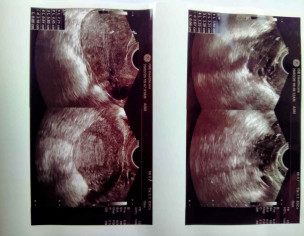

Talk to Gynecologist on Bilateral Polycystic Ovaries

I have been married for 12 years. I have one daughter 11 years old. But, after that I haven't had a baby yet .Sending in my wife's report

Attach Photo here: